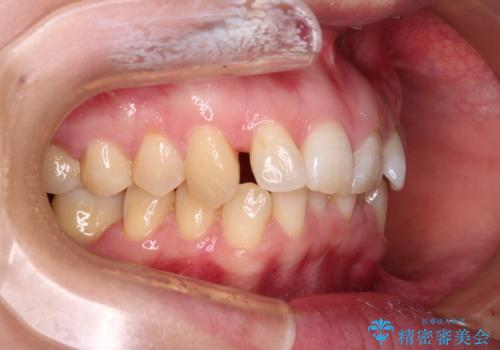

- 上顎前歯の前方に傾斜した咬み合わせを気にして来院された患者様です。

奥歯の咬み合わせを見ると、上顎が下顎に対して相対的に前方にありました。

深い咬み合わせを改善するためには、上顎臼歯を後方に移動させつつ、下顎の小臼歯を直立させる必要があります。

インビザライン単体で対応ることも検討できますが、達成する可能性が低いため、カリエールディスタライザーという補助装置を併用して、より確実性を上げることとしました。

奥歯の咬み合わせと深い咬み合わせを改善した後、インビザラインで歯列を整えることとしました。